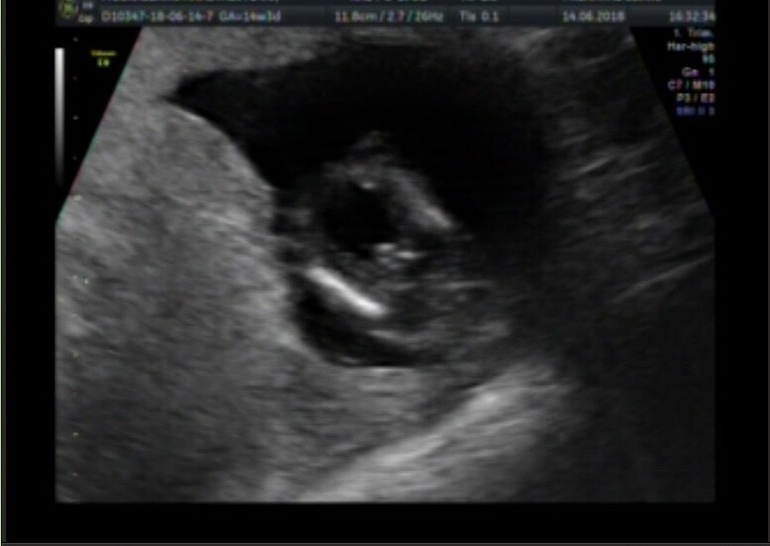

Анжелика Крекотень

Срок 15 недель.мне дали такое фото,думаете есть вероятность ошибки?